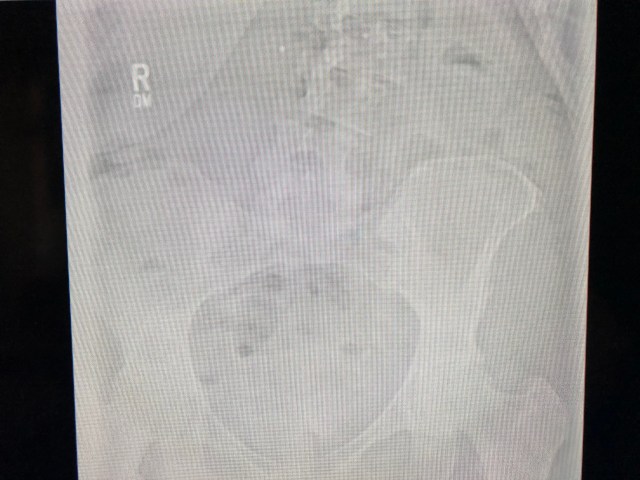

The most problematic issue has been my spine. I have scoliosis and it has gotten markedly worse over the past few years while working as a professional driver.

Here are some recent x-rays of my back: